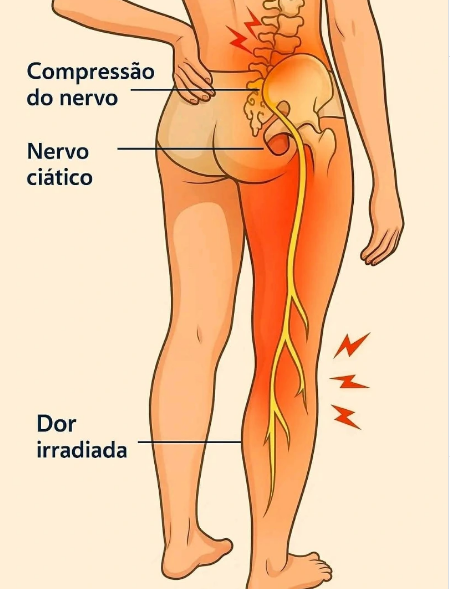

O nervo ciático é o maior nervo do corpo humano e percorre desde a região lombar até os pés. Quando há compressão ou tensão excessiva nos músculos e na fáscia — tecido que envolve e conecta as estruturas do corpo — podem surgir dores intensas, sensação de formigamento, queimação ou limitação de movimento.

A Liberação Miofascial atua diretamente nesses tecidos, utilizando pressões específicas e movimentos lentos para reduzir aderências, melhorar a mobilidade muscular e diminuir a compressão sobre o nervo. Durante o atendimento, são trabalhadas principalmente regiões como lombar, glúteos e parte posterior das pernas, áreas frequentemente relacionadas ao desconforto do ciático.